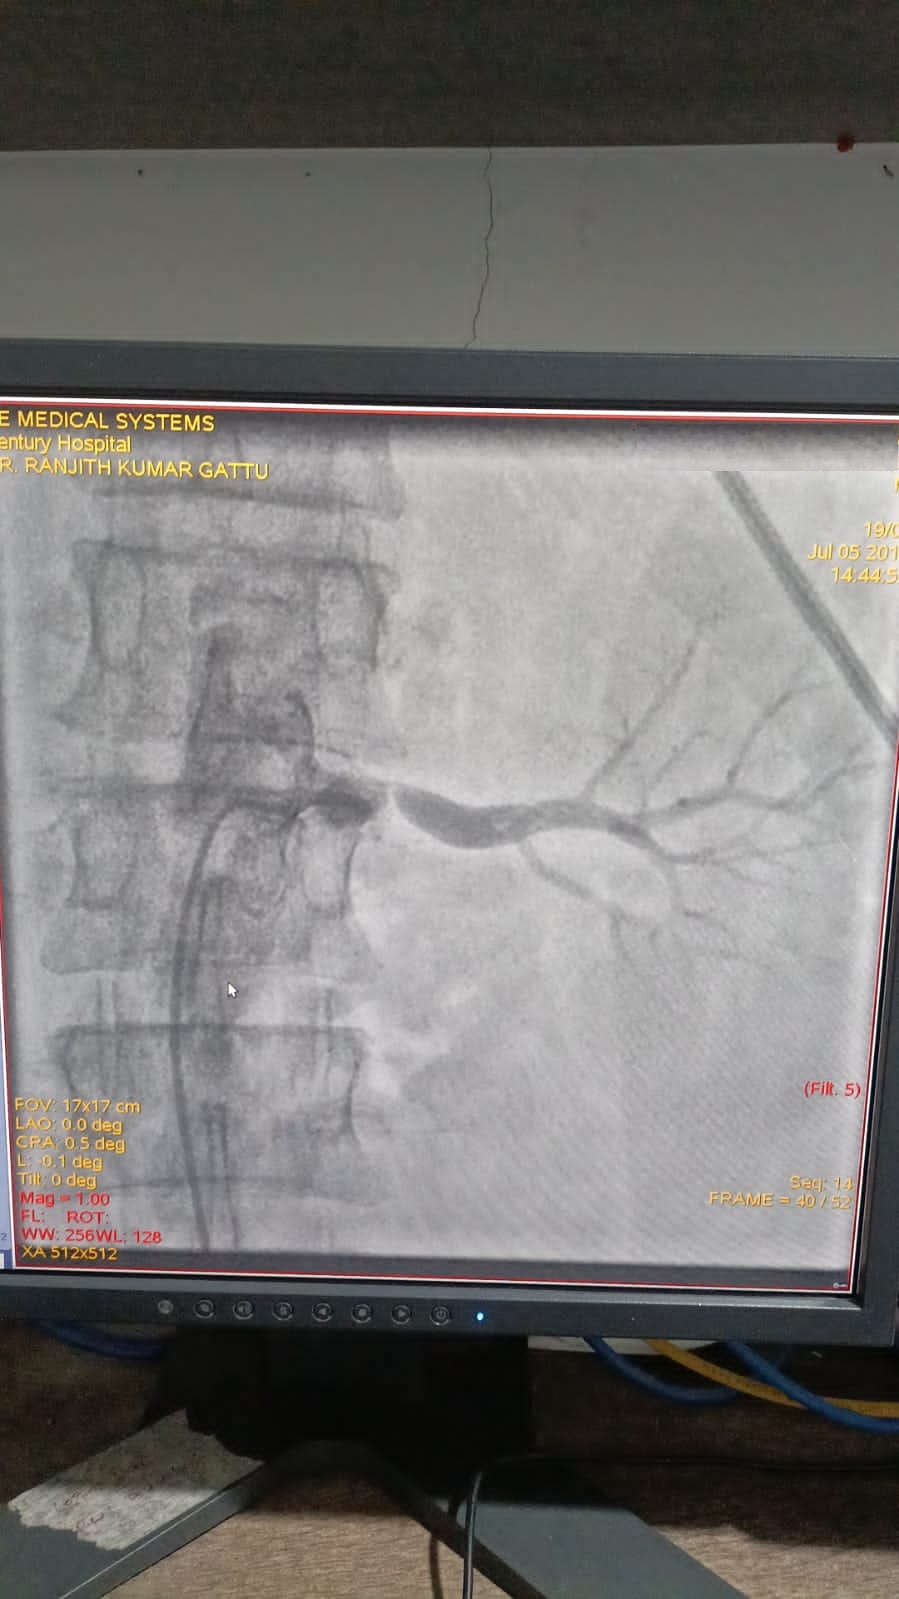

Right Coronary Diseased Artery